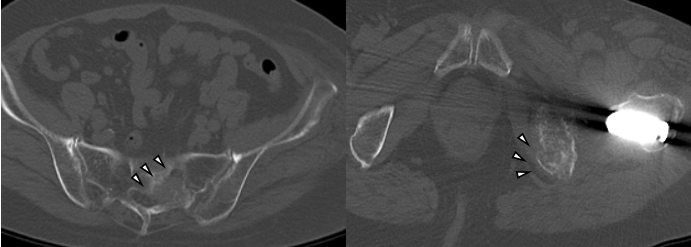

Although she was able sit in a wheelchair, her pain became intolerable. The patient and her family strongly requested surgical intervention for pain relief. Pre-operative computed tomography (CT) and MRI demonstrated metastatic bone destruction involving the left acetabulum and extending toward the ischium (Fig. 4).

Figure 4: Pre-operative computed tomography (CT) (left, axial view) and magnetic resonance imaging (MRI) (right, axial view). The axial CT view shows osteolytic metastatic destruction extending from the acetabulum toward the ischium (arrows). The axial T1-weighted MRI view demonstrates a metastatic lesion involving the superior acetabular dome, corresponding to the weight-bearing region (arrowheads).